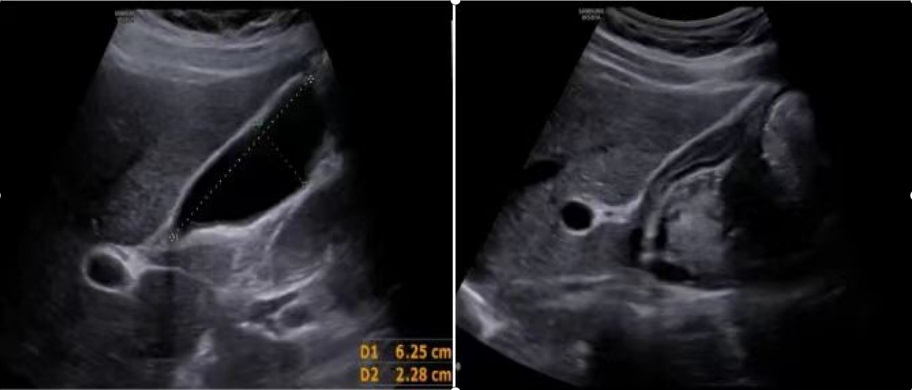

空腹时,超声下显示胆囊壁光滑,胆囊内透声好,未见明显异常(左图)进食后,胆囊收缩,胆囊壁增厚,内部情况显示不清(上图)